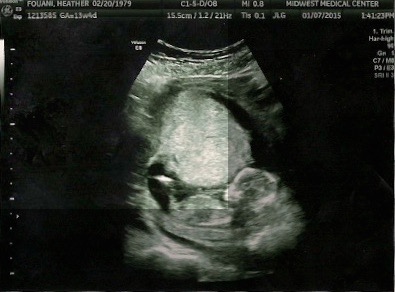

A profile shot at 13 weeks 4 days. The tech was old school and said she has never heard of the nub theory but gave me a profile shot, but I'm not even sure if it's showing anything. I think I might see a boy nub compared to my searches and comparisons online (but maybe it's a leg) hmmmm. Anyone have any guesses? Also I will be sure to update when confirmed for the future reference of others. Attachment 22917Attachment 22918